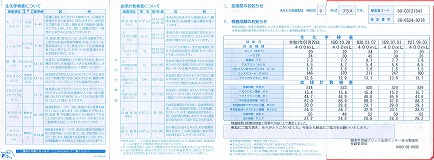

0104 ②2018.09.03 =PDF

②

①

①0207-1.jpg)

0207-2.jpg)

0102 2017.08.22 PDF

健診P1

健診P1

健診P2

健診P2

0100 2015.10.05 PDF

健診P1

健診P1

健診P2

健診P2